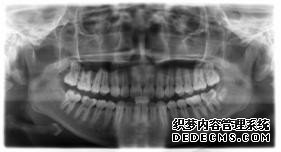

临床诊断:通过3D数字化全景机的检查,患者的上牙前突属于牙性,双唇闭合时可见明显隆起,X片显示根尖无异常,上下后牙存在间隙,可通过美国MBT直弓丝正畸技术将其矫正复位,并收拢间隙,矫正所需时间一年半左右。

全景机正位片